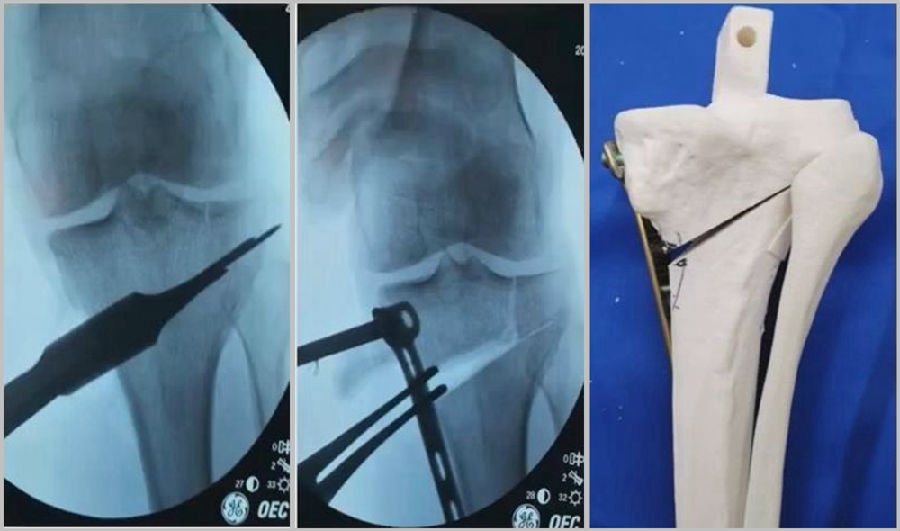

首先要把截骨撑开钳拿下来,此时骨折端会自动复位,然后再由外向内侧打入一颗拉力螺钉,将胫骨平台做临时固定,然后再进一步的用摆锯锯或是用骨刀打,保留1cm的合页,最后再进行撑开,做内固定。同样要求患者做结构植骨加延迟负重。

截骨偏前,截骨线过短;Ⅲ型骨折;保留1cm合页

结构植骨,外侧拉力钉固定